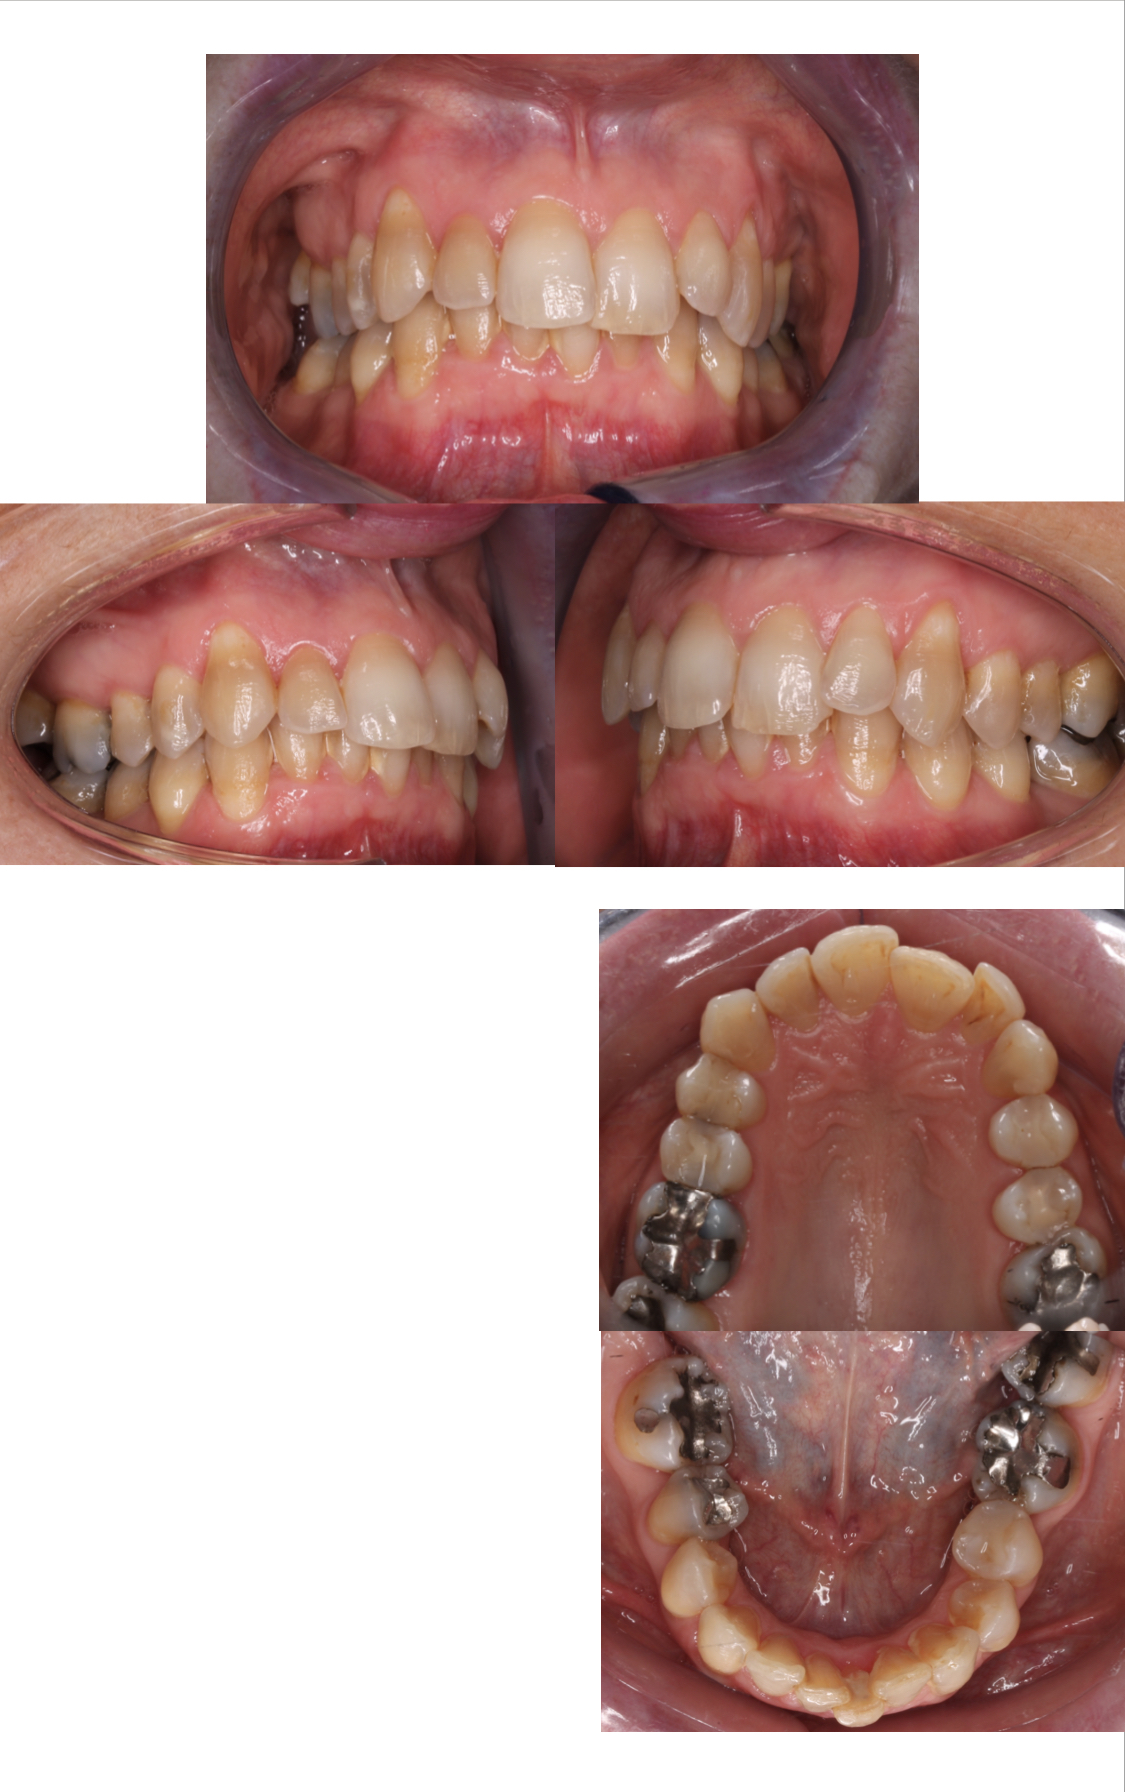

• La pianificazione 3D scanner guidata da parte dell’ortodontista dei micro-movimenti di ogni singolo dente che devono essere eseguiti al fine di ottenere l’occlusione perfetta.

• La progettazione di una o più serie di allineatori costituiti da materiali brevettati INVISALIGN in grado di trasferire forze in tempi ed intesità specifiche che il paziente dovrà cambiare seguendo le indicazioni dello specialista. In alcune situazioni verranno inseriti piccoli attacchi in resina, poi rimossi a fine trattamento, per aiutare gli allineatori ad eseguire anche i movimenti più difficili.

• Registrazione e avanzamento.

• Controlli periodici con cadenza mensile durante tutto il periodo di trattamento.

• Un ulteriore scansione 3D e serie di allineatori se dopo aver terminato il trattamento sarà necessario perfezionare alcuni aspetti del sorriso.